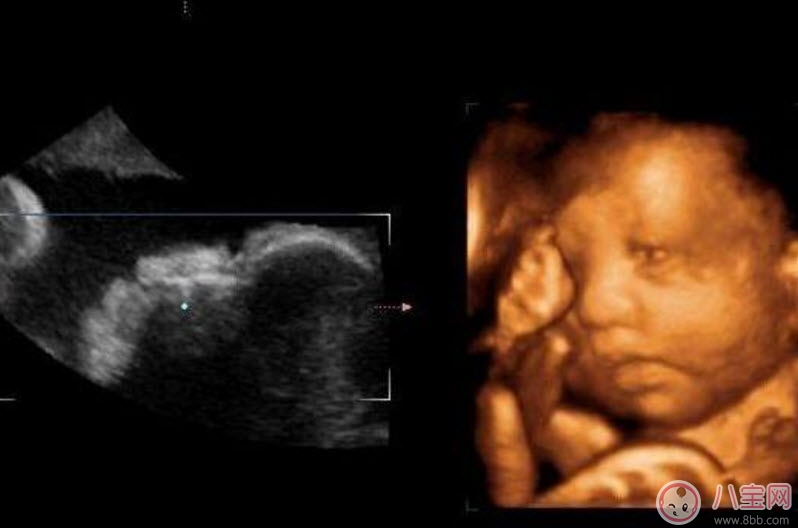

四維彩超的全稱是四維彩色超聲診斷儀,是世界上最先進的彩色超聲設備。四維彩超能夠表面成像,可以更佳清晰的查出來胎兒的四肢發育是否畸形,腦膜膨出,是否唇腭裂、脊柱裂等先天畸形,及早發現及早的做出解決方案。

二維超聲可以理解為我們通常說的B超,顯示的是斷面圖像。何為斷面圖像?就是把西瓜切開,你在屏幕上只能看到西瓜的切面(斷面),但經驗豐富的你,可以只看這個切面(斷面)就知道這是一個西瓜。

三維、四維超聲就是把很多個二維斷面圖像通過計算機重建成一個立體的圖像。相當于把切成很多片的西瓜,重新堆疊成一個完整的西瓜,這個堆疊過程由計算機完成。三維、四維的區別在于,三維是照片,四維是影片,四維就是會動的三維照片(實時三維)。